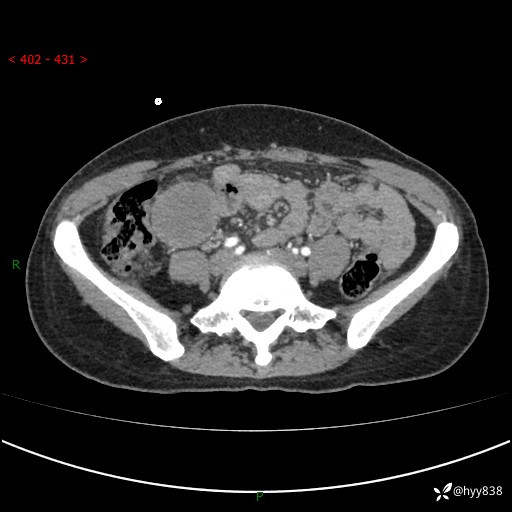

年轻女性,发现腹腔肿物1周。圆圆的肿物,诊断有难度---结果公布~

现病史:患者自诉于1周前无明显诱因出现剑突下间断性隐痛,尚可忍受,不向其它部位放射,无恶心呕吐、腹泻便秘等不适,于当地市第二人民医院就诊,行CT结果示:1.右中腹占位,间叶组织来源可能2.小肠梗阻3.盆腔积液4.腹腔积液5.副脾6.肝囊肿;于荆州二医行抗炎,抑酸,护胃,补液等对症支持治疗;患者病情好转,今为求进一步诊治,遂来我院门诊就诊,门诊以“腹腔肿瘤”收入院。 起病以来,患者精神、睡眠、饮食一般,大小便正常,近期体力体重无明显改变。

腹部CT增强(外院平扫)